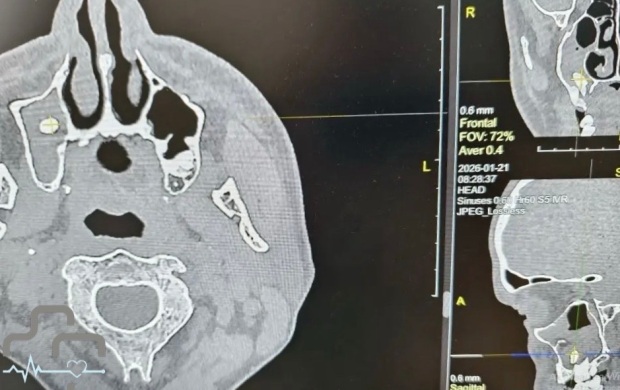

В Орске мужчина обратился в больницу с жалобами на затрудненное дыхание. Оказалось, что в его носовой пазухе оказался зуб. Об этом сообщили на странице во "ВКонтакте" городской больницы Орска.

Выяснилось, что ранее мужчина удалил зуб. В медучреждении объяснили, что такое случается, когда при удалении зуба происходит нарушение целостности костной перегородки, отделяющей зубной ряд от носовой пазухи, из-за чего зуб или его фрагмент могут сместиться в пазуху.

У пациента зуб проник так глубоко, что это повлияло на дыхание.